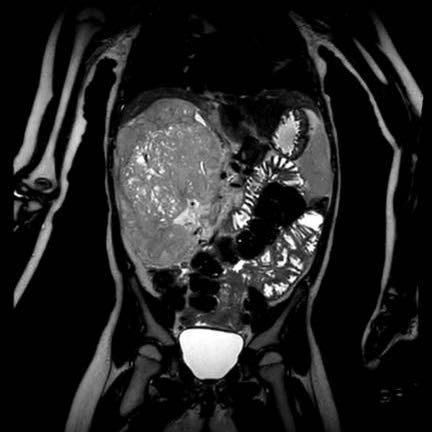

Ca lâm sàng 1

Hình ảnh chuỗi xung T2W mặt phẳng coronal cho thấy một khối u không đồng nhất ở thận trái với các thành phần nang nhỏ.

Khối u ngấm thuốc kém hơn so với phần nhu mô thận bình thường còn lại ở ngoại vi.

Các thành phần đặc của khối u cho thấy hạn chế khuếch tán rõ rệt (mũi tên).

Đây là u Wilms ở bé trai năm tuổi. Hóa trị tiền phẫu được thực hiện theo phác đồ Umbrella của SIOP-RTSG, sau đó tiến hành cắt thận.